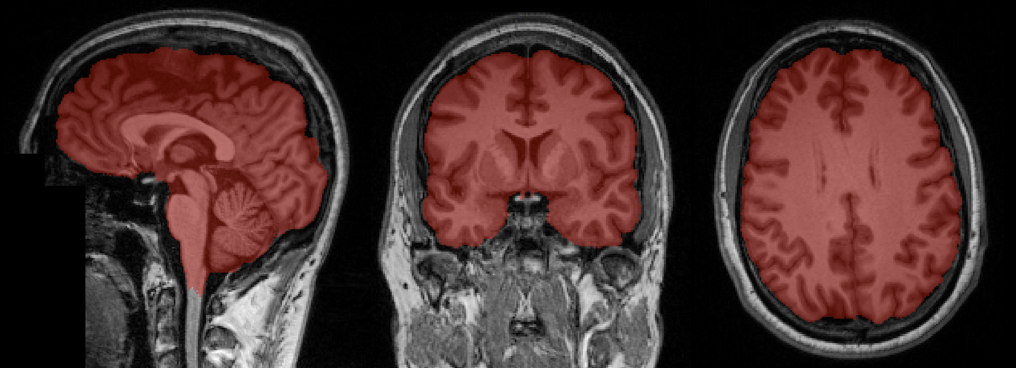

Refer to caption

Figure 2: Example of brain extraction using the proposed CNN. Best viewed in color.

In Figure 2 an example of the obtained segmentation of the brain tissue is illustrated.